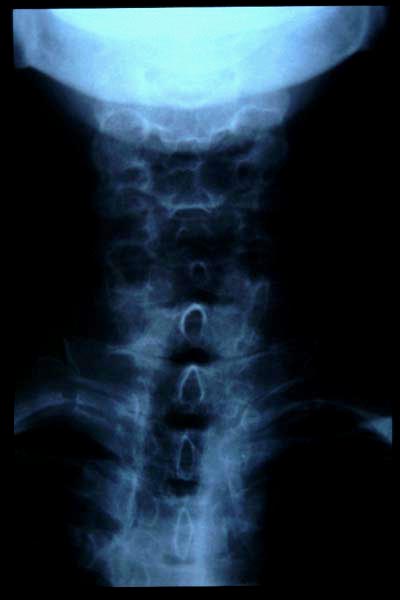

Artrosis cervical.

Artrosis cervical

APR Cervicoartrosis